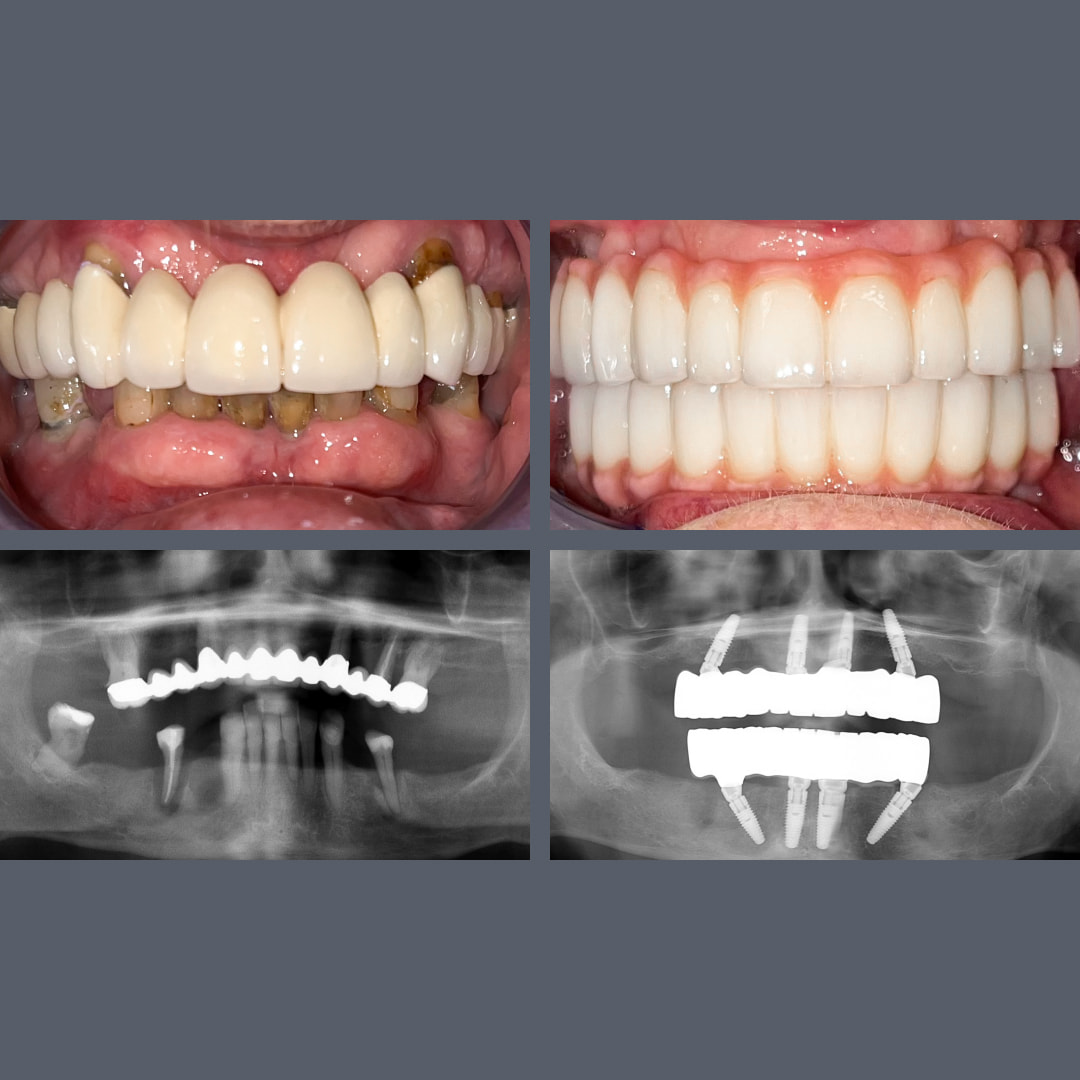

Tandkødssygdom, uoprettelige tænder? – All-on-4®, fast protese på 48 timer